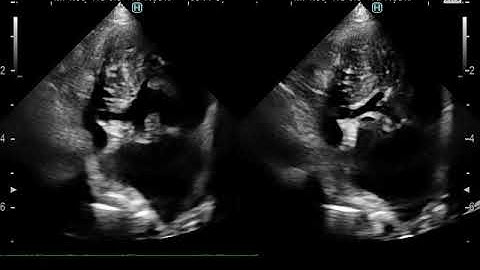

Azygos Continuity and Persistent Left SVC